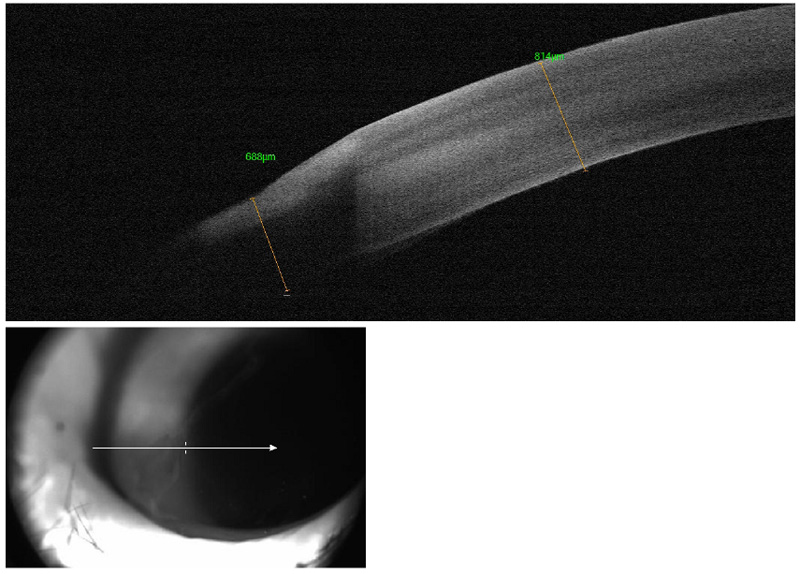

Con el fin de conocer con precisión la profundidad de las lesiones corneales, se realizó una prueba complementaria llamada Tomografía de Coherencia Óptica (OCT) determinándose que dichas lesiones no presentaban gran profundidad.